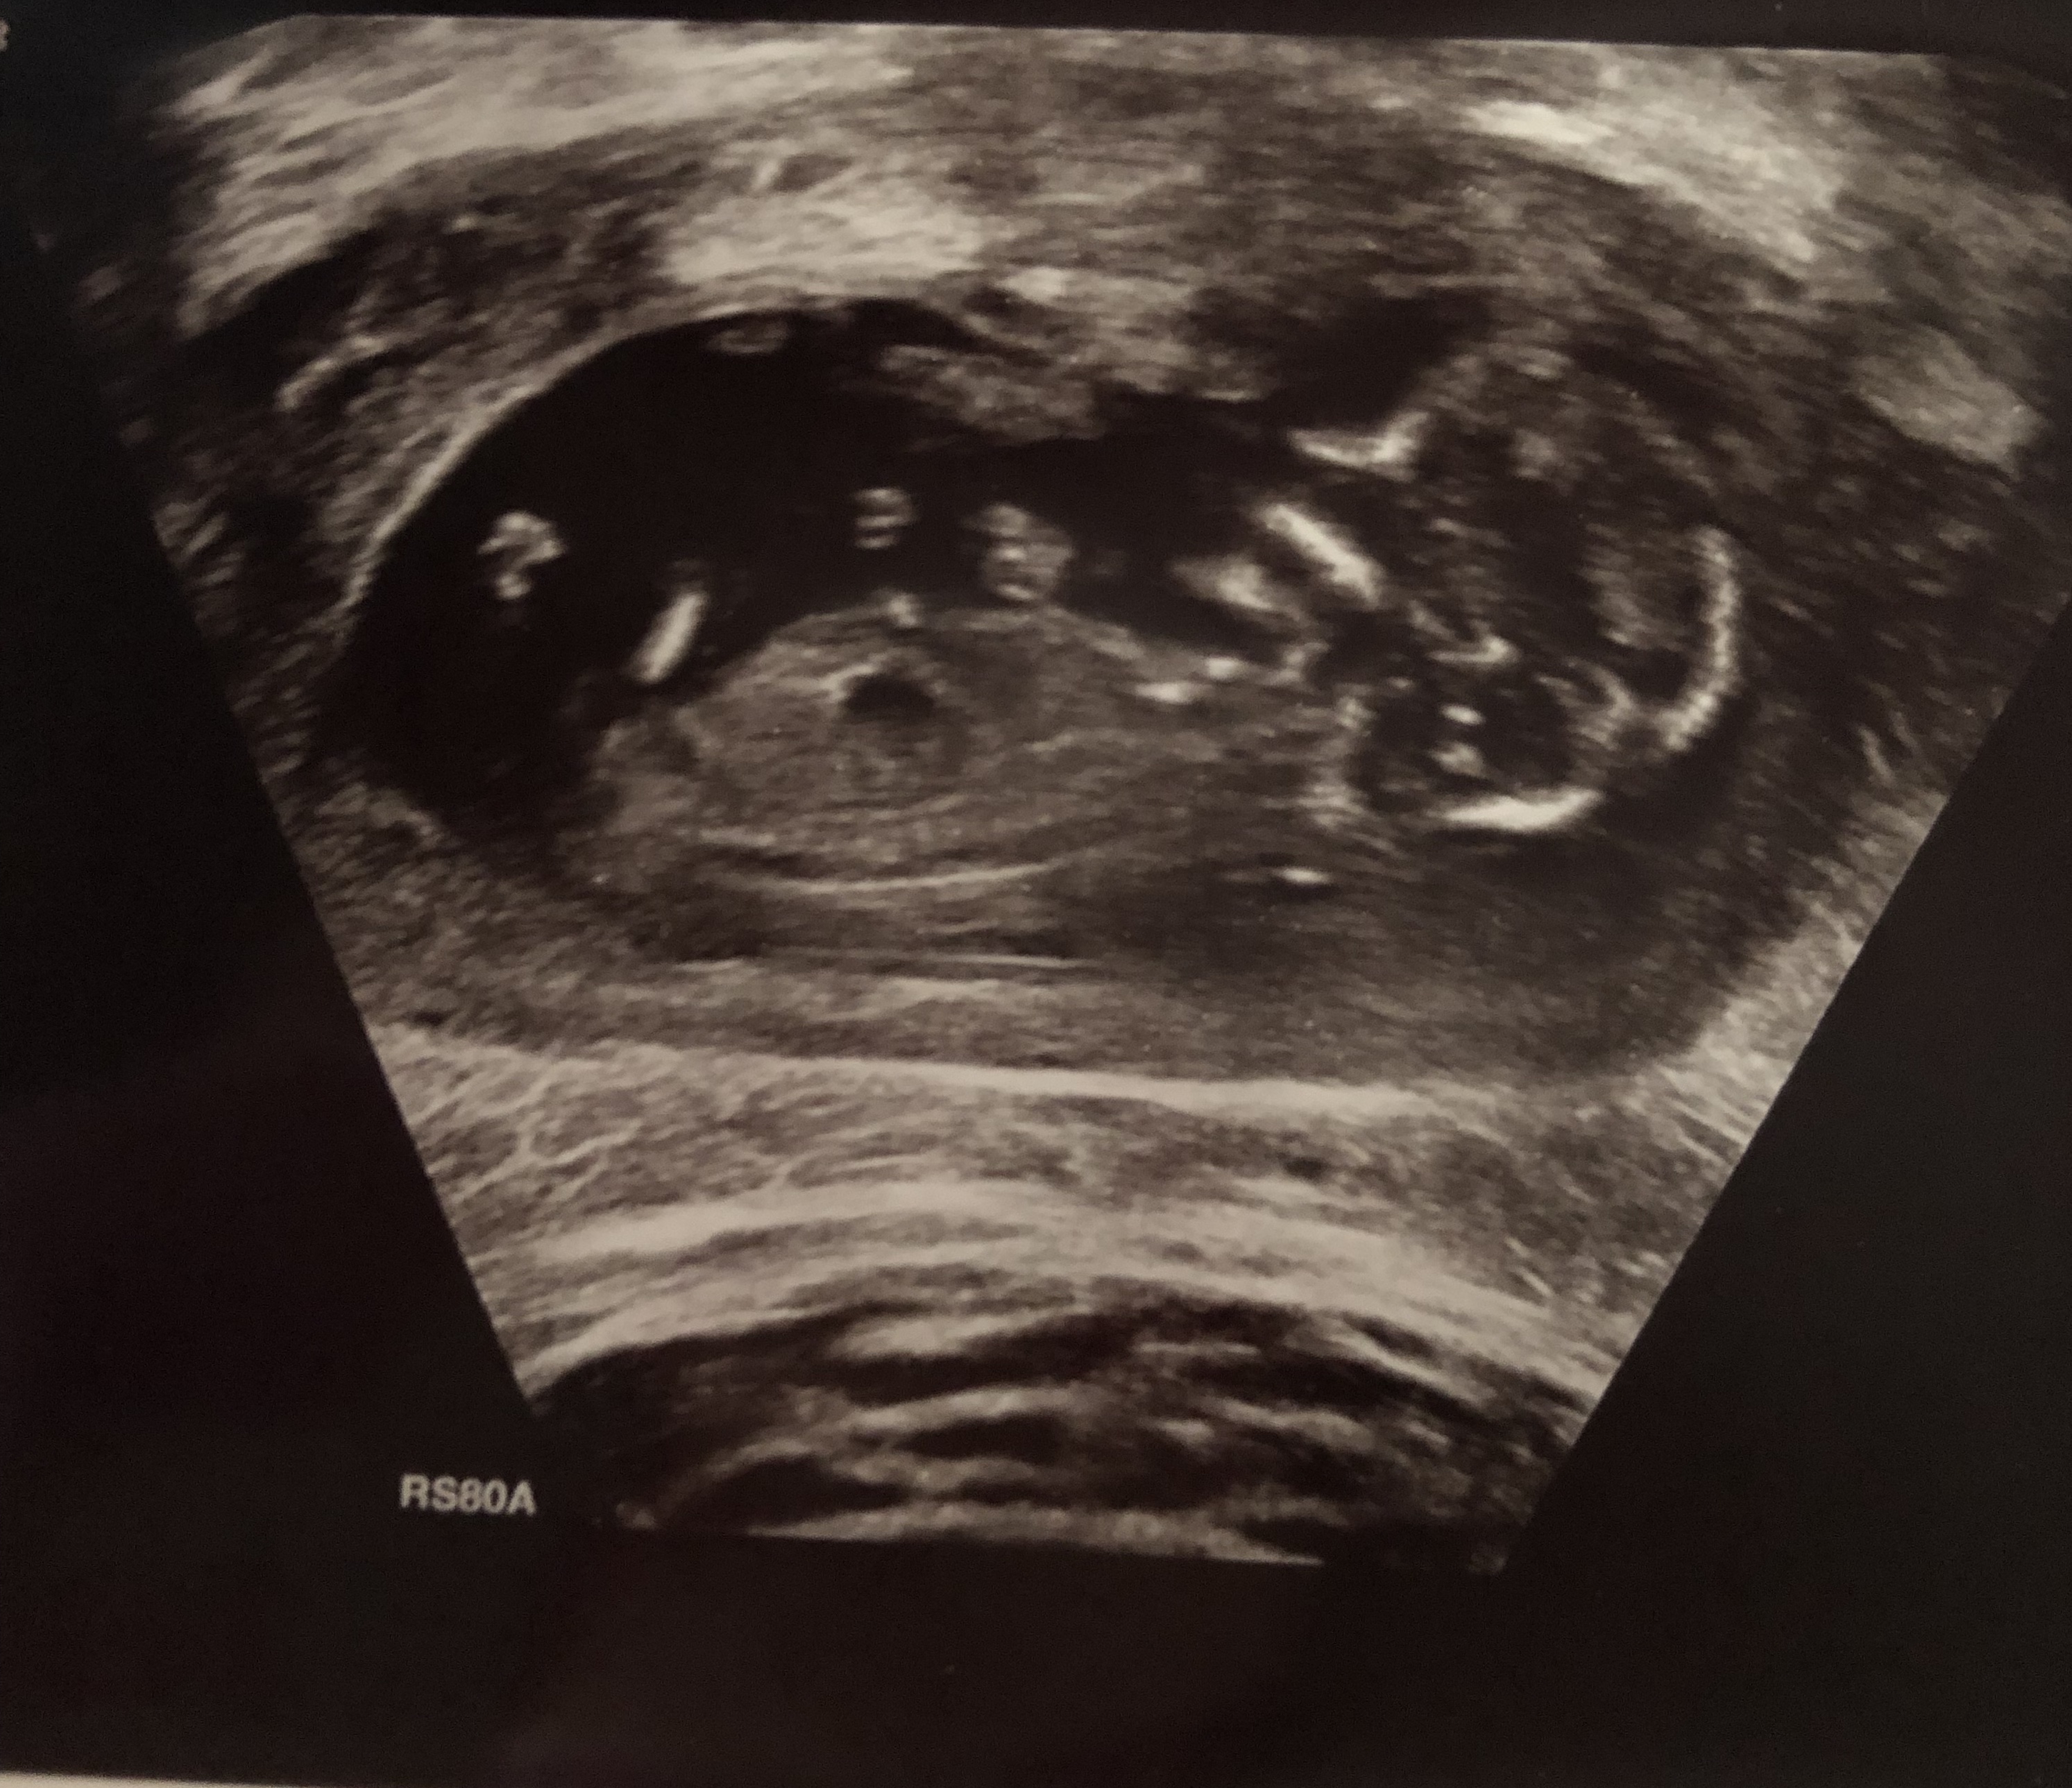

Hi could anyone guess for me please? Is the nub the part that I have circled that looks like a fork? Thanks x Attachment 41518Attachment 41518

Ok thanks I do have This pic also not sure if it’s any better? xAttachment 41526

I don't see a nub in these.